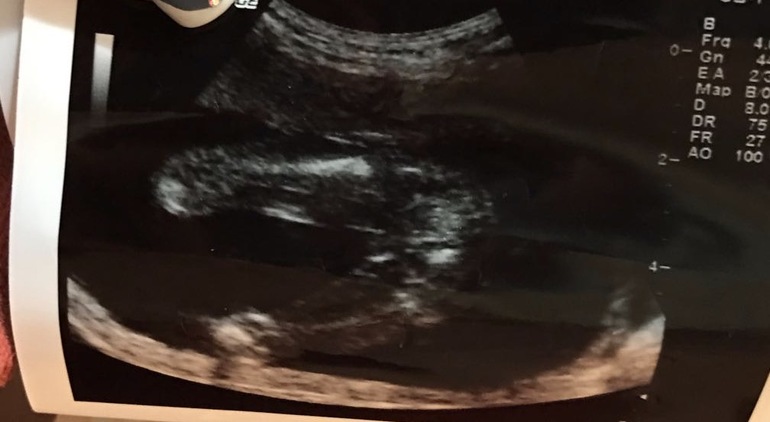

Вот наша сосиска

но фото это с 14 недель

надеюсь вы разобрались где что)))

Я поняла так. Две ножки, а посередине перчик. Верно?

именно)))

Вот у нас с вами похожии,но мне врач говорит ,что девочка.фото УЗИ 19+3 ,а у вас?

у нас 14 недель...но у вас правда девочка...